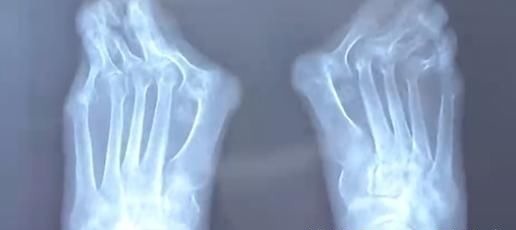

由于高跟鞋的挤压,王女士的左脚大脚趾变成了两个脚趾,随着时间的推移,大脚趾一侧又多了一个 \\\\'\\\\'拐\\\\'\\\\',现在只能通过手术来缓解症状。除了鞋子不当,遗传和疾病因素也是造成拇指外翻的原因,70 岁的高女士患风湿病,脚也发生了接近 60 度的严重变形。

忍痛十几年,直到前几天,高女士连男士的鞋子都穿不上,眼看着不能走路了才来到医院就诊,而这时手术的风险和难度都增大很多。